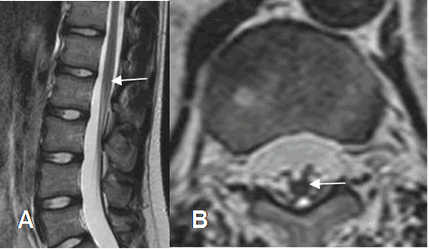

Fig 23. Cono medular.

A: RM sagital en T2. Cono medular normal, entre L1 y L2.

B: RM axial en T2. Como medular normal, con apariencia de araña.